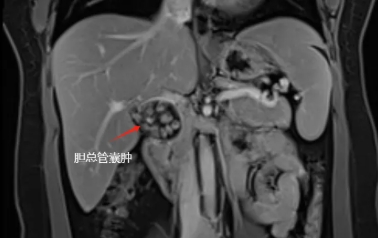

检查结果显示

胆总管内有一肿物

且里面装满胆石

最终入院后确诊为先天性胆总管囊肿Ia型,我院肝胆外科卢明柱主任团队为患者提供了详细的治疗方案——微创手术切除畸形扩张的胆管,该手术创伤小,恢复快,疗效确切,单女士欣然接受手术方案,并于近日实施了手术(腹腔镜下胆总管囊肿切除+胆囊切除+肝总管空肠Rou-en-Y吻合)。目前,单女士术后恢复良好,已顺利出院。